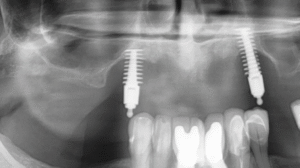

Can You Remove Dental Implants? Everything You Need to Know

Many people worry about what happens if their dental implant causes pain or doesn’t fit right. It’s natural to wonder if these implants can be...

Bone Graft at Time of Implant Placement: Saving You Months and Keeping Your Smile

You’ve lost a tooth, and your dentist mentions you might need a bone graft. But here’s the good news—you might not have to wait months...